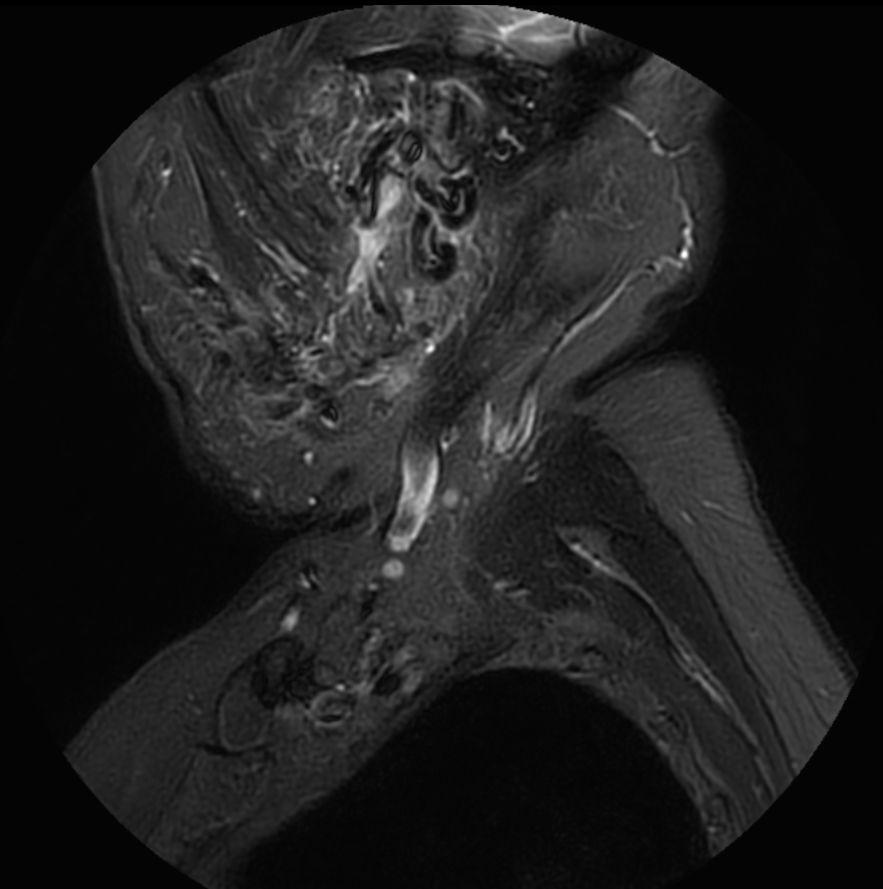

STIR MultiVane XD